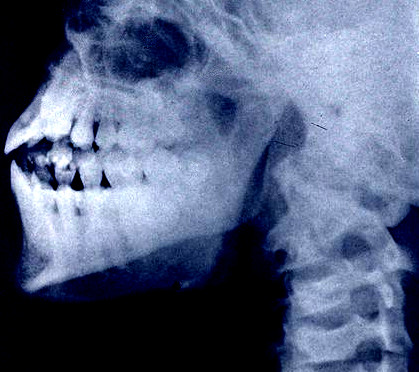

对象全身遍布多处磨损与皮肤撕脱伤。多处骨折与骨碎,特别是沿上颌骨与鼻骨。3颗牙齿(2颗上颚,1颗下颚)破碎。

内部检验:内生殖器官缺失。前额叶严重偏小;杏仁核严重肥大。以髋骨确认性别(女)。肺组织表现出急性低氧性缺氧。